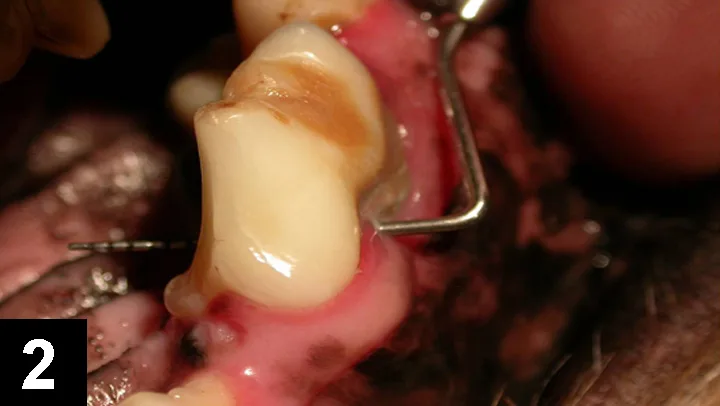

Periodontal Flap SurgeryAs pockets deepen, cleaning becomes more difficult and surface irregularities increase, complicating closed periodontal therapy.4-6 Consequently, pockets deeper than 5- to 6-mm (Figure 1) require direct root visualization for effective cleaning7 because residual calculus is often seen in such pockets (Figure 2).8

Featured Image

Figure 2: Maxillary right canine (#104) in a dog: This patient presented with an 8-mm periodontal pocket. A “full” periodontal flap (with 2 vertical releasing incisions) was performed after closed root scaling. Note the residual calculus that is now visible for cleaning.